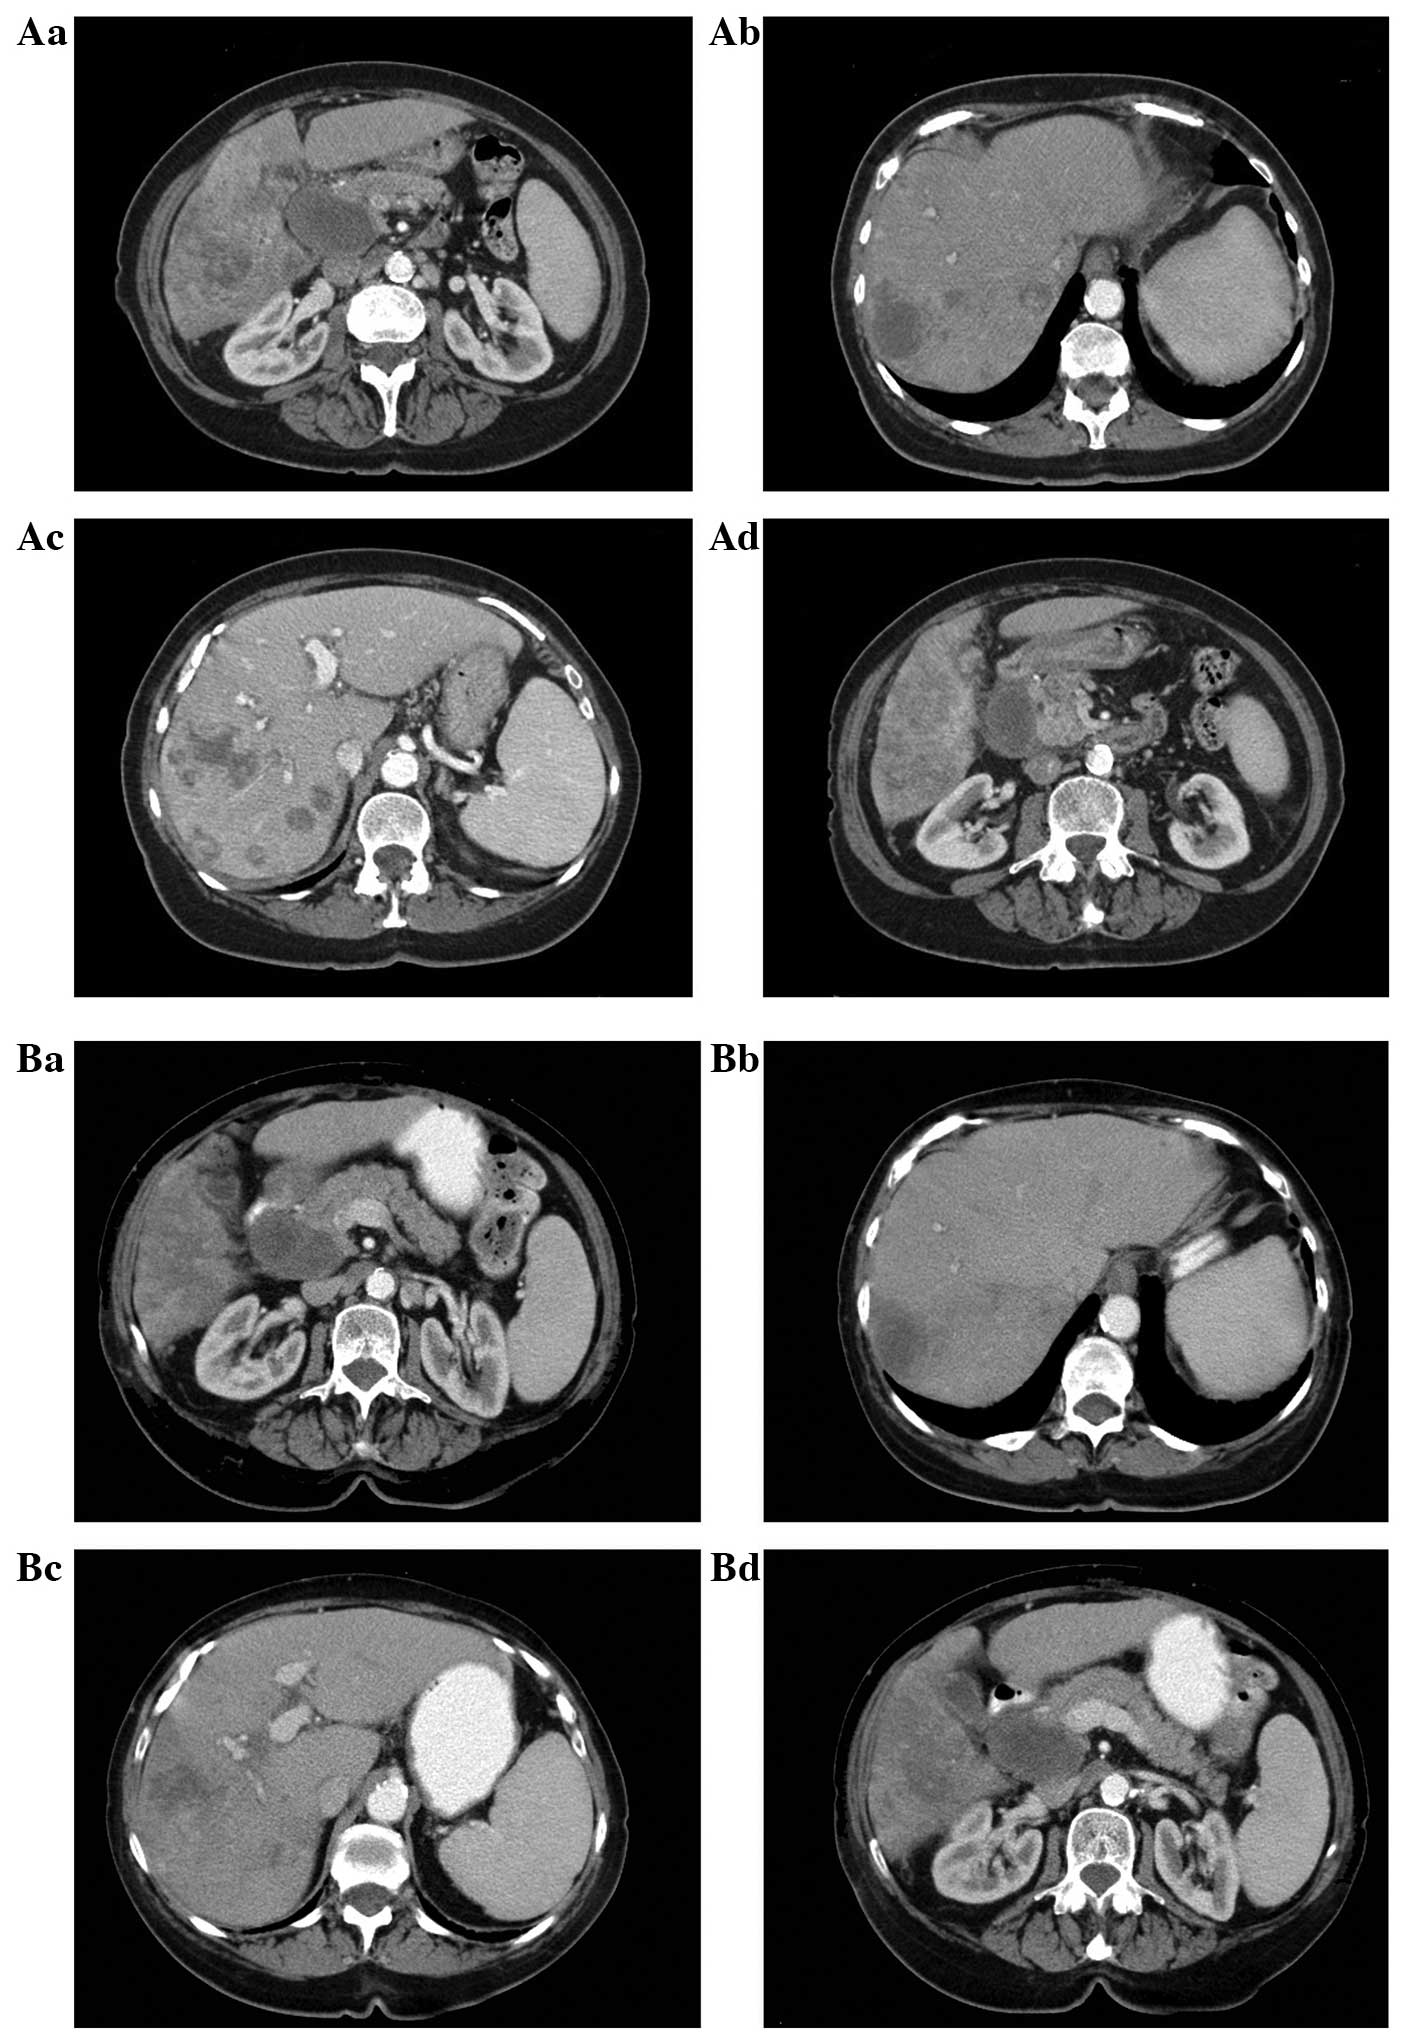

Pancreatic Cancer Ct Scan - Pancreatic cancer, CT scan - Stock Image - C037/8292 ... - Pancreatic cancer will typically refer to ductal carcinoma of the pancreas, which comprises up to 90% of primary pancreatic malignancies.

Pancreatic Cancer Ct Scan - Pancreatic cancer, CT scan - Stock Image - C037/8292 ... - Pancreatic cancer will typically refer to ductal carcinoma of the pancreas, which comprises up to 90% of primary pancreatic malignancies.. The abdominal ct scan may show problems with the gallbladder, liver, or pancreas, including Pancreatic cancer (cancer of the pancreas) mainly occurs in people aged over 60. A ct scan is one of the most common tests for pancreatic cancer. A pet scan is often done in combination with a ct scan. Why aren't pancreatic ct scans used in routine physical examinations to detect and prevent the spread of pancreatic cancer?

A ct scan is often used as the primary test to diagnose or confirm pancreatic cancer. Effectiveness of ct scan for pancreatic cancer detection. Ct scans create pictures of your pancreas, gallbladder, and bile ducts. Learn how this test works, as well as its benefits and risks. Many cancer centers use a special ct scan method called a pancreatic protocol ct scan.

Before the scan, dye is injected into a vein to help make the pictures clearer. Ct scans help doctors diagnose and treat medical conditions such as pancreatic cancer. Ct scans are usually done at a hospital or a radiology clinic. This method focuses on taking pictures of the pancreas at specific. From my experience as the patient being diagnosed…. Ct scans can show pancreatitis or pancreatic cancer. Learn how this test works, as well as its benefits and risks. How do ct scans work? Contrast is a special dye used to make it easier. Ct scans are often performed to monitor patients after treatment to determine whether the cancer has recurred, changed in size or metastasized this test is not as specific as ct scanning and is not used alone to diagnose pancreatic cancer. A contrast dye injected at the start of the here are some other challenges to finding pancreatic cancer early: A ct scan is often used as the primary test to diagnose or confirm pancreatic cancer. Doctors commonly order ct scans if they think a person may have pancreatic cancer.

Ct scans can also be used to guide a biopsy needle into a suspected pancreatic tumor. Learn how this test works, as well as its benefits and risks. Ct scanning will visualize the vast majority of pancreatic cancers, and it provides important information to guide treatment. Many cancer centers use a special ct scan method called a pancreatic protocol ct scan. Why aren't pancreatic ct scans used in routine physical examinations to detect and prevent the spread of pancreatic cancer?

This provides a series of images from many different angles. Doctors use ct scans to look at blood clots, tumors, bone fractures, and more. Abdominal ct scan can provide a more detailed analysis of the pancreas and other abdominal organs and is much more accurate than ultrasound in detecting pancreatic cancer, with a sensitivity of about 90%. A ct scan can be helpful both for characterizing the tumor (determining its size and location in the pancreas) and looking for any evidence of spread to lymph nodes or other. Pet/ct fusion scan enhances ct staging in patients with pancreatic. Effectiveness of ct scan for pancreatic cancer detection. Ct scans are usually done at a hospital or a radiology clinic. Ct scanning will visualize the vast majority of pancreatic cancers, and it provides important information to guide treatment.

This depends on the reason for your ct scan and which part of your body your doctor needs to see. A contrast dye injected at the start of the here are some other challenges to finding pancreatic cancer early: Pancreatic cancer — overview covers symptoms, risk factors, prevention, diagnosis, surgery, chemotherapy and other treatment for cancer of several types of growths can occur in the pancreas, including cancerous and noncancerous tumors. A precontrast scan of the pancreas can be performed to look for calcifications within the pancreas, which may indicate the presence of a focal pancreatitis. A ct scan is often used as the primary test to diagnose or confirm pancreatic cancer. Effectiveness of ct scan for pancreatic cancer detection. A computerised tomography (ct) scan is a commonly used test to assess pancreatic cancer. Abdominal ct scan can provide a more detailed analysis of the pancreas and other abdominal organs and is much more accurate than ultrasound in detecting pancreatic cancer, with a sensitivity of about 90%. Ct scans are usually done at a hospital or a radiology clinic. Why aren't pancreatic ct scans used in routine physical examinations to detect and prevent the spread of pancreatic cancer? Ct scans can show pancreatitis or pancreatic cancer. Multidetector ct scanning (mdct) using a pancreas protocol is at least as accurate as eus in the overall determination of the resectability of pancreatic algorithm for evaluation of a patient with suspected pancreatic cancer. Contrast is a special dye used to make it easier.

Pancreatic cancer — overview covers symptoms, risk factors, prevention, diagnosis, surgery, chemotherapy and other treatment for cancer of several types of growths can occur in the pancreas, including cancerous and noncancerous tumors. A ct scan can be helpful both for characterizing the tumor (determining its size and location in the pancreas) and looking for any evidence of spread to lymph nodes or other. For evaluating possible pancreatic cancer, a multiphase helical ct scan or pancreatic protocol ct scan is often recommended. Pancreatic cancer versus chronic pancreatitis: Ct scans are usually done at a hospital or a radiology clinic.

This provides a series of images from many different angles. It takes pictures from different angles. Many cancer centers use a special ct scan method called a pancreatic protocol ct scan. Pancreatic cancer (cancer of the pancreas) mainly occurs in people aged over 60. Ct scans can also be used to guide a biopsy needle into a suspected pancreatic tumor. Ct scanning will visualize the vast majority of pancreatic cancers, and it provides important information to guide treatment. The ct scans, four of them over the course of the 11 weeks from my initial appointment with my primary (23 march). A ct scan is one of the most common tests for pancreatic cancer. It can show the pancreas it also helps doctors know how extensively cancer has spread in the pancreas. How do ct scans work? The most common type of cancer that forms in the. The abdominal ct scan may show problems with the gallbladder, liver, or pancreas, including For evaluating possible pancreatic cancer, a multiphase helical ct scan or pancreatic protocol ct scan is often recommended.